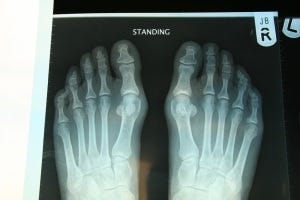

When I got back to London, I went in for x-rays on my foot to see what was really going on. Much to our (pleasant) surprise, the joint space in the big toe was much better than we thought, but we thought we should get an opinion from Dr. Lowell Scott Weil Sr., an expert foot and ankle surgeon based in Chicago, to see what my surgical options were.

Dr. Weil saw that there was some deformity in my right big toe. If you look closely at my x-ray above, you can see that the right big toe angles in toward my other toes more so than the left big toe (fancy name: hallux valgus). Dr. Weil said it didn't look TOO bad, but it sounded like I had tried all other methods (orthotics, manual therapy, injections) and surgery would help.

I've been doing a bit of research to figure out the implications of having a sesamoid bone removed. I had never heard of things strange little bones before - how important could they really be??? Turns out, a lot. If you look at the xray below, you may see two pea-shaped bones under each first toe. They look like little floating balls. These are the sesamoids - the inner one is the medial/tibial and the outer one is the lateral/fibular. They are located under the head of the first metatarsal (remember, the big toe joint) and in the tendons of the flexor hallucis brevis muscle.